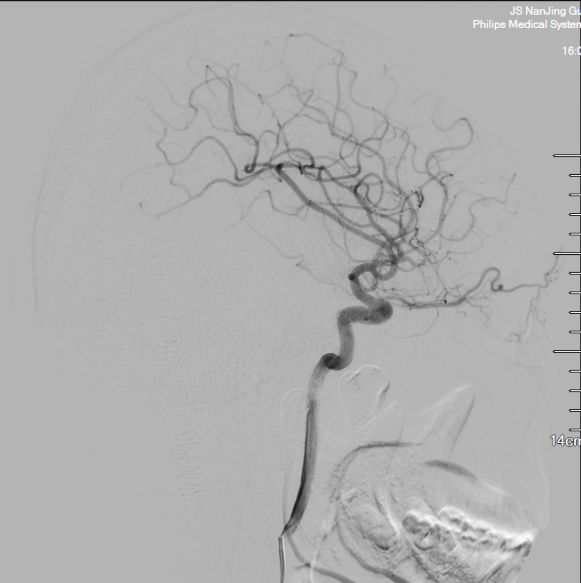

患者于2017年9月无明显诱因下出现右下肢无力,症状逐渐加重,在当地医院行膝关节核磁共振检查未见明显异常,3个月后至南京大学医学院附属鼓楼医院神经内科就诊,给予营养神经等对症治疗,并完善相关检查,肌电图示双下肢部分神经源性损害,双上肢未见明显异常;脊髓MR(本院,2017-12-16)示C5-T2层面脊髓明显增粗伴信号异常,颈髓及上段胸髓周围多发迂曲增粗血管影,考虑血管畸形伴脊髓脱髓鞘改变可能(图1)。入院查体:T36.4℃,P76次/分,R18次/分,BP105/78mmHg。双上肢肌力5级,双下肢4级,四肢肌张力正常,生理反射存在,病理反射未引出。入院初步诊断:脊髓血管畸形。

图1. 颈髓MRI蛛网膜下腔血管流空影(白色箭头)与脊髓水肿(黑色箭头)